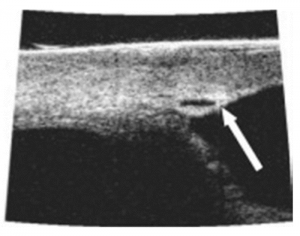

Lewis' study reported only 16 adverse events in 12 eyes using the ab-externo technique. Mild hyphema is common and was seen in 10.2% of eyes and all except in 3 eyes were resolved by 1 month. Figure 16 A Descemet detachment with intrastromal corneal blood was seen in 3.2% of eyes. Figure 17 3 eyes had persistent IOP elevated > 30 within the first 90 days. 2 were converted to trabeculectomies and 1 underwent YAG goniopucture. Figure 18A and Figure 18B 7 eyes had increased IOP in the late postoperative course of which 5 required procedures including goniopuncture, iridoplasty, cyclophotocoagulation, and a trabeculectomy. There was only a 0.6% rate of early hypotony but there were no flat anterior chamber, choroidal detachment, or endophthalmitis reported.[12]